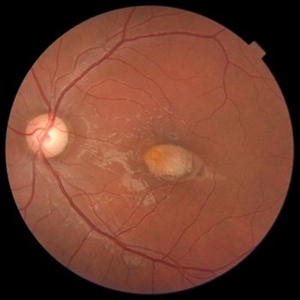

RAM With Garland of Hard Exudate

Fundus Photo of left eye of 75-year-old female with retinal artery macroaneurysm at superior quadrant with garland like hard exudates.

Photographer: KRISHNENDU NANDI

Imaging device: Topcon

Condition/keywords: hard exudates, retinal arterial macroaneurysm